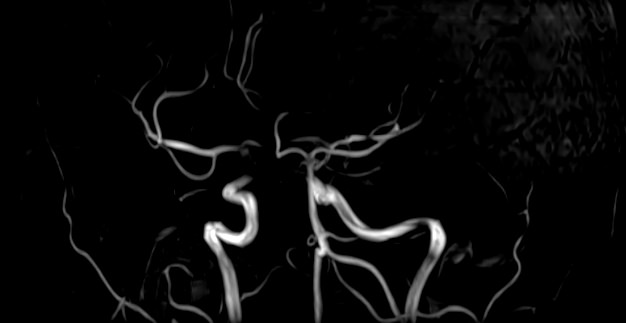

МР-артериография — неинвазивный безопасный метод исследования для диагностики патологии артериальной системы головного мозга. Магнитно-резонансная артериография позволяет получить трехмерное изображение сосудистой системы, кровоснабжающей центральную нервную систему, оценить анатомическое строение артерий головного мозга и функциональные особенности кровотока.

С помощью электромагнитных волн томограф послойно сканирует структуры исследуемого органа, затем посредством компьютерных программ преобразует полученные данные в трехмерное изображение. При этом на снимке видна только сосудистая система без окружающих тканей. Таким образом, сканирование в режиме ангиографии позволяет визуализировать артерии и вены головного мозга без контрастирования.